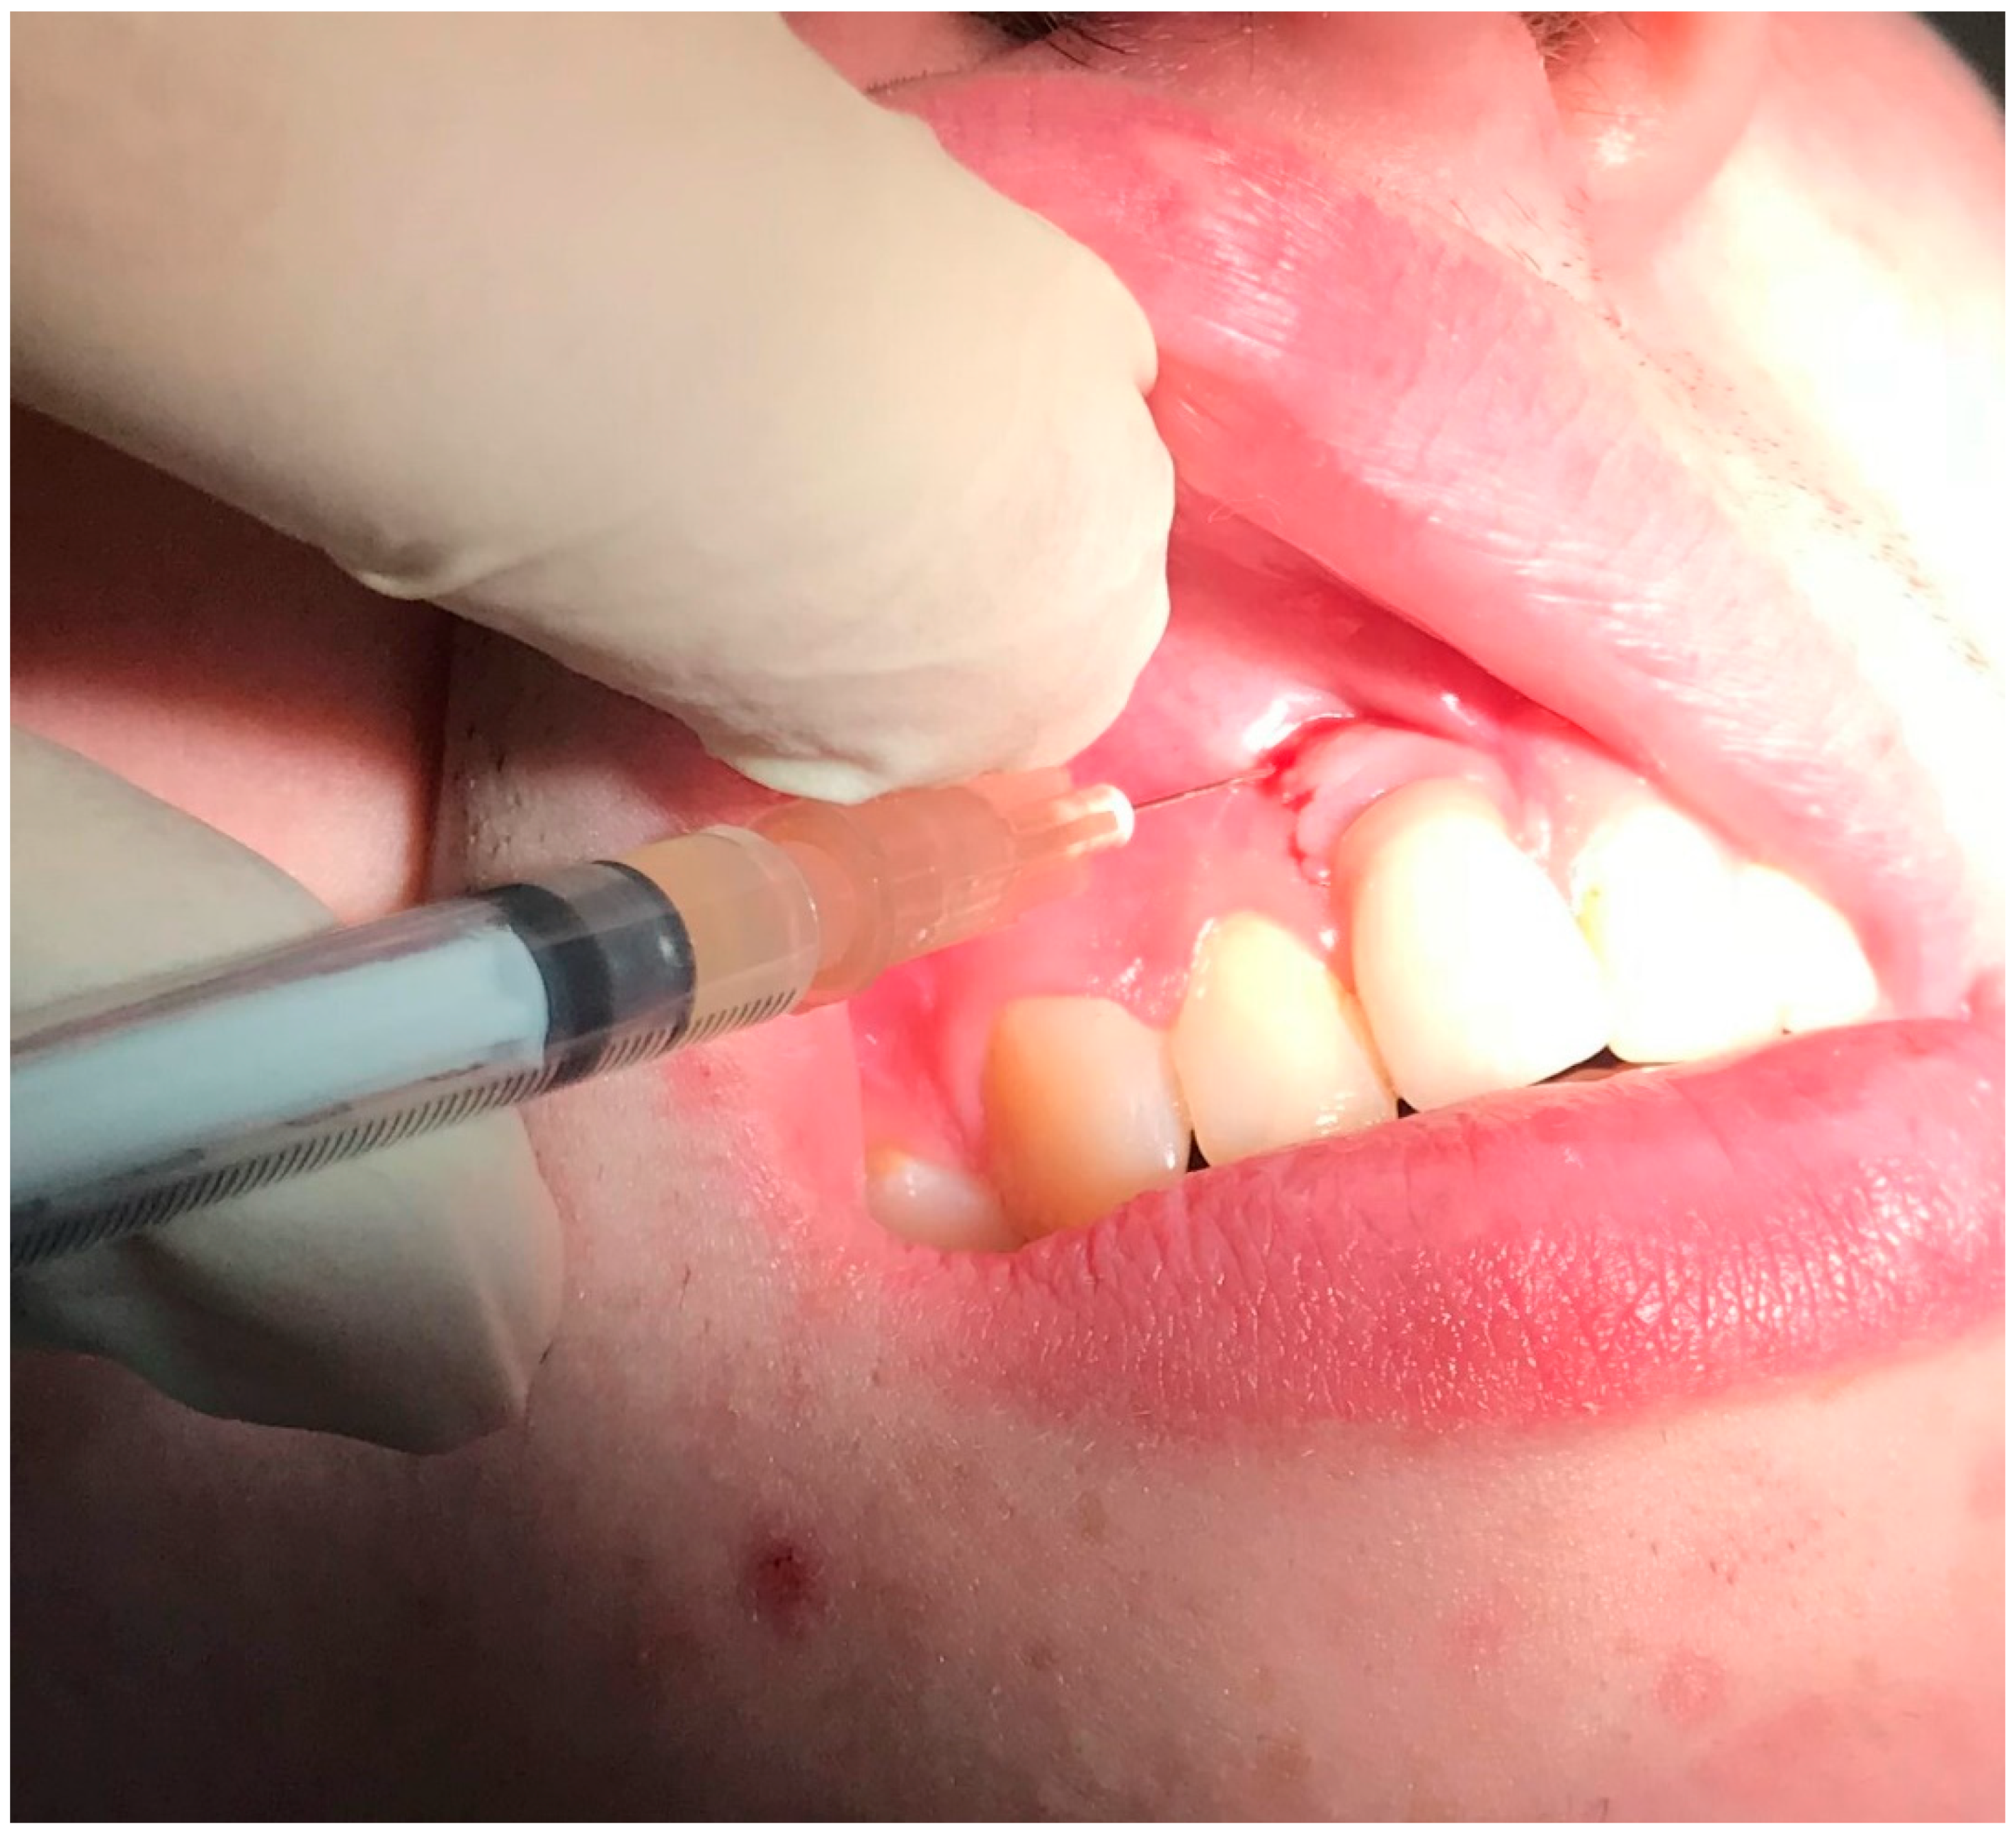

2.1. Case Report 1

2.2. Case Report 2

2.3. Case Report 3